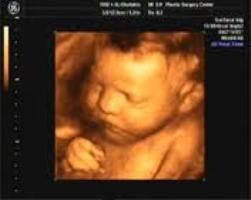

да ну, бросьте, как нельзя то? вам там все покажут все органы, ручки, ножки. на вашем сроке вам покажут вот такое e2e6f7750f118fe802cd08a34ef7528c.jpg  а после 30 вот такое, еще  ведео дадут, любую часть тела покажут)и в уменбшеном виде, но все же такое изображение куда симпотичнее  9d744064cd983f7f2cbc421b83ae5760.jpg